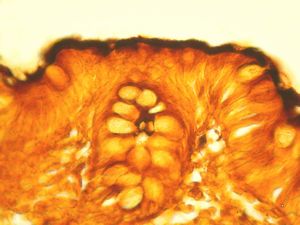

F,68y. | caecum - carcinoid